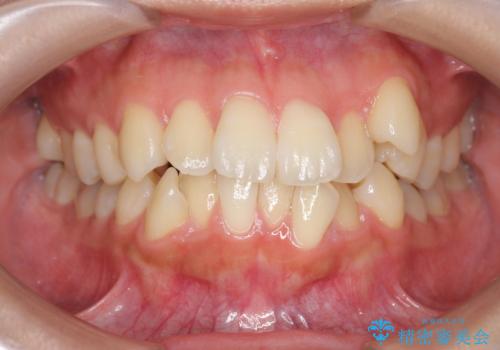

八重歯を矯正治療で治したい!